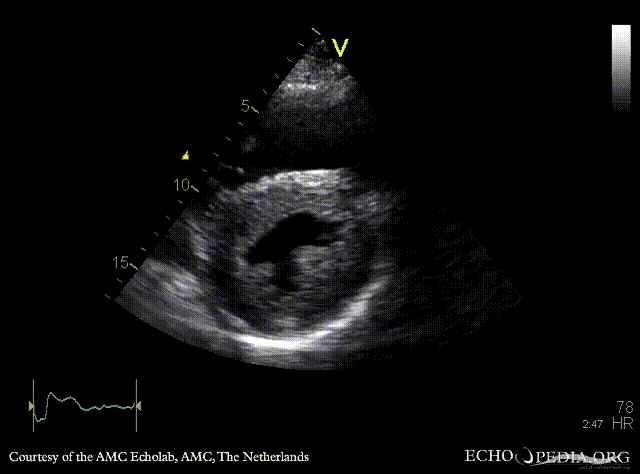

Amyloidosis

PLAX: concentric left ventricle hypertrophy in a patient with amyloidosis PSAX: concentric left and right ventricle hypertrophy